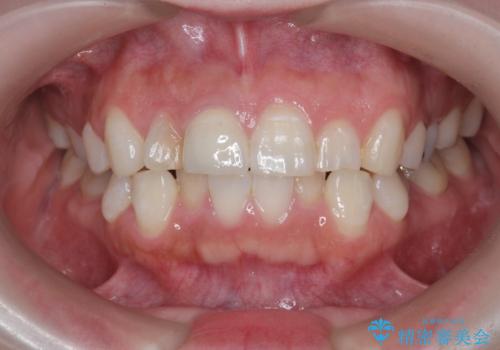

前歯の変色 セラミッククラウンによる審美性の回復

根尖に病変は見られず、根管治療は行わずに仮歯・ジルコニアクラウンを作製、装着することで審美性を回復しました。

- 12.1万円 (仮歯・ジルコニアクラウン)費用は治療当時の料金となります

神経の治療を行った歯は、徐々に変色し審美障害をきたすことはから当院ではセラミッククラウンの装着をお勧めしております。